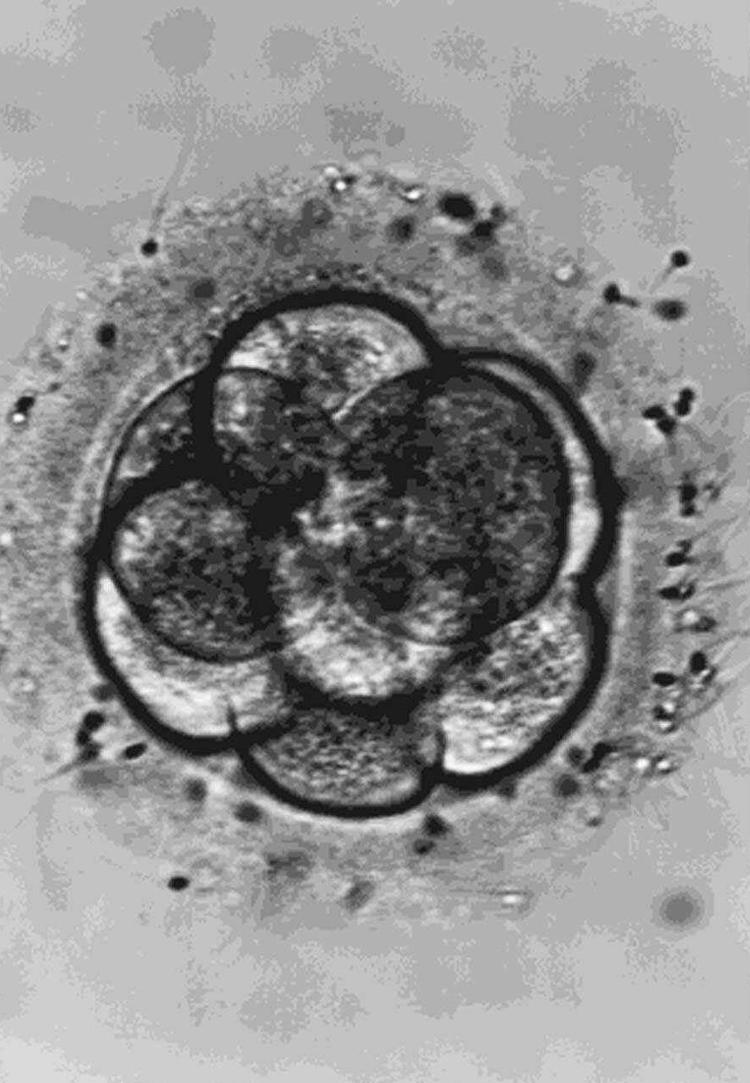

Videnskabsmænd fra Newcastle siger, at de som de første i verden har skabt kunstige menneskelige sædceller.

I tidsskriftet Stem Cells and Development skriver forskerne ifølge BBC News, at der vil gå mindst fem år, før teknikken er færdigudviklet og kan bruges til at hjælpe mænd, der har problemer med deres forplantningsevne.